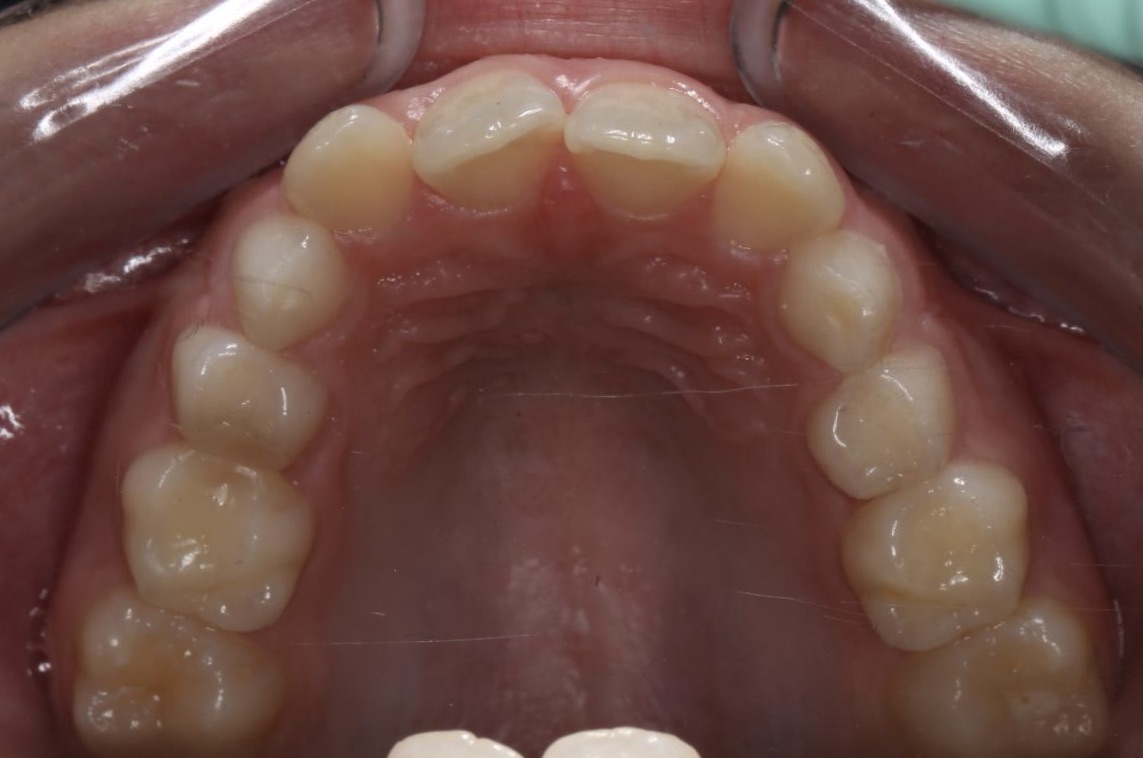

Na de verbreding is de kruisbeet opgeheven, de onderkaak bijt weer recht in de bovenkaak en we weten dat de hoektanden veel meer ruimte zullen ervaren als ze willen doorbreken.

De tijd tussen smal en breed is hier maar 6 weken, waarin om de dag versteld werd.